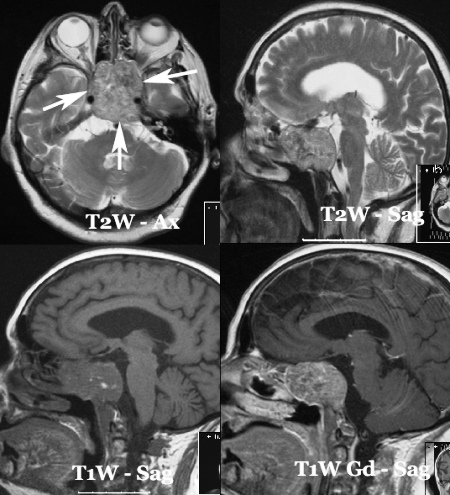

Chordoma is a rare slow-growing malignant neoplasm thought to arise from cellular remnants of the notochord. Chordomas can arise from bone in the skull base and anywhere along the spine. The two most common locations are cranially at the clivus and in the sacrum at the bottom of the spine.

There are three histological variants of chordoma: classical, chondroid and dedifferentiated. Chondroid chordomas appear to have a more indolent clinical course . In most cases, complete surgical resection followed by radiation therapy offers the best chance of long-term control. Incomplete resection of the primary tumor makes controlling the disease more difficult and increases the odds of recurrence.Chordomas are relatively radioresistant, requiring high doses of radiation to be controlled